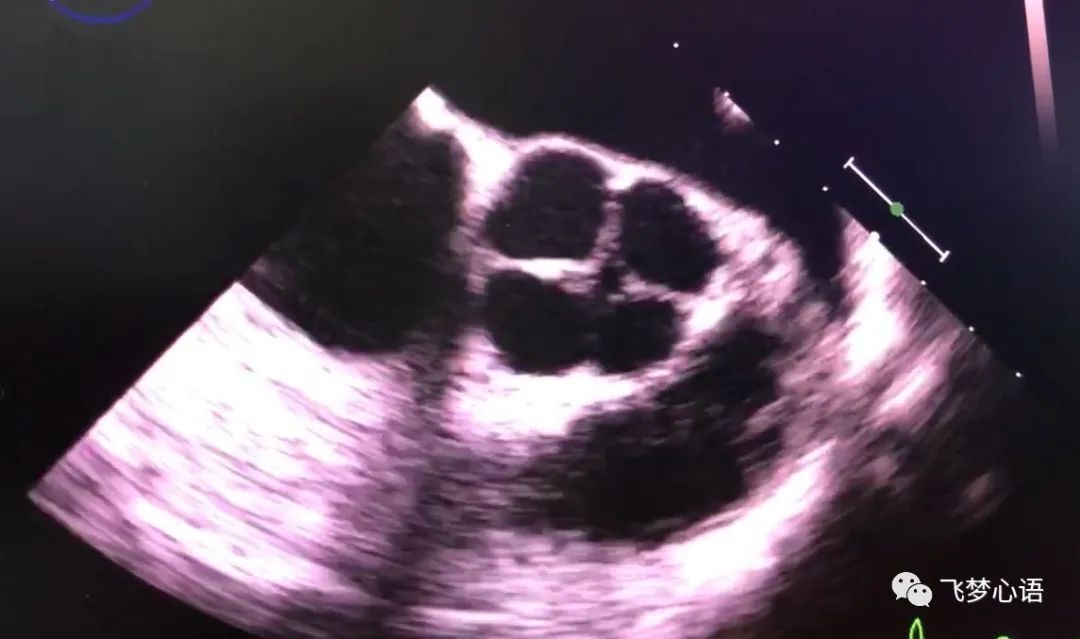

正常主動(dòng)脈瓣為三個(gè)瓣葉,但人群中有1%~2%的人發(fā)育成二個(gè)瓣葉,還有極少數(shù)人發(fā)育成四個(gè)瓣葉,先天性主動(dòng)脈瓣四瓣化畸形非常罕見,其發(fā)病率約0.008%-0.013%。系胚胎期瓣膜發(fā)育障礙所致,胚胎早期動(dòng)脈干分割為主、肺動(dòng)脈兩條大血管后,在瓣葉形成過(guò)程中由于動(dòng)脈干的內(nèi)膜隆起發(fā)育不良,造成瓣葉發(fā)育異常,該病多見于男性。主動(dòng)脈瓣四瓣化畸形的瓣葉易脫垂,或瓣葉緣增厚攣縮,導(dǎo)致主動(dòng)脈瓣關(guān)閉不全,達(dá)到中重度關(guān)閉不全時(shí),需外科手術(shù)行主動(dòng)脈瓣置換,根據(jù)年齡和患者需求選擇機(jī)械瓣或生物瓣。四瓣葉畸形外觀很像我們小時(shí)候玩的“東南西北”折紙。主動(dòng)脈瓣四瓣化的心臟彩超圖